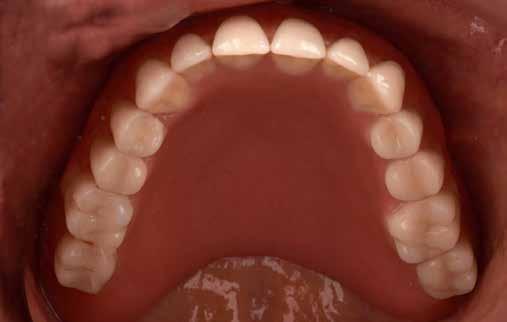

Az IOS adatok felhasználása, mintanyomtatás

A digitális lenyomatvételt (4. kép) követően a primer részek előállításához a CAD szoftverben vágatlan fogívet szegmensekre osztottuk, és a pontosság ellenőrzésére csonkokat generáltunk (5-6. képek). Az ebből nyert STL-adatállományt virtuálisan illesztettük a 3D nyomtató építőasztalára (7. kép), és a Bego cég VarseoWax Model segítségével Anycubic Photon Mono X LCD-nyomtatóval kinyomtattuk a mintákat (8. kép)

5–6. képek: Kész intraorális szkennelések.